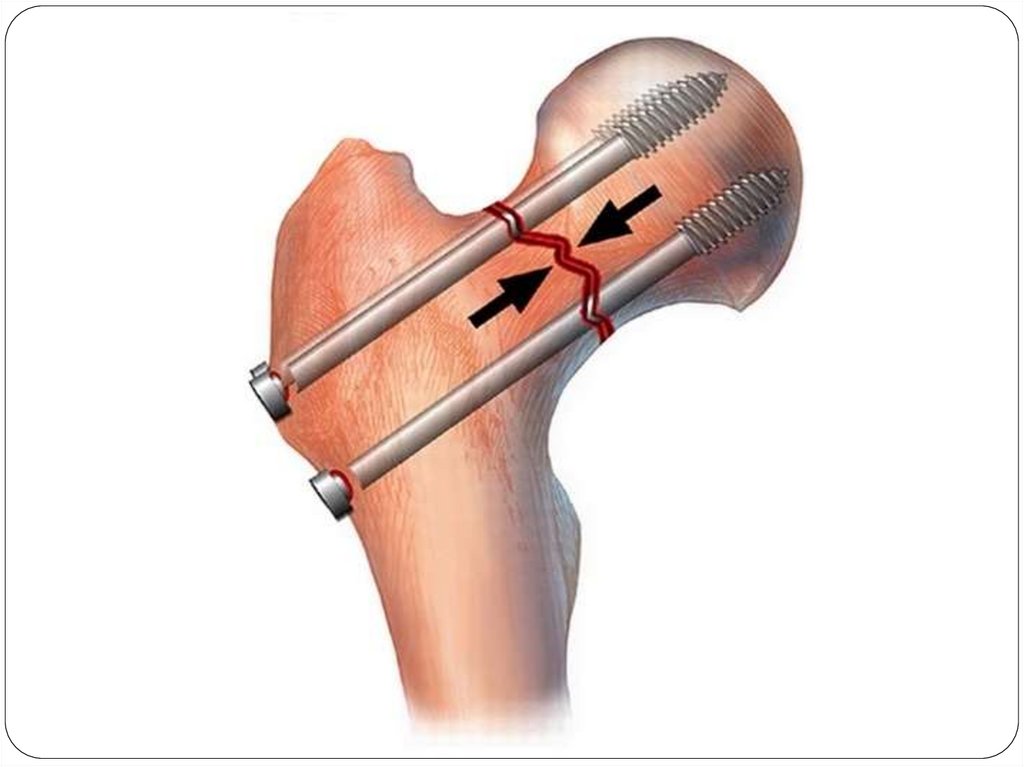

Различают 2 основных вида

остеосинтеза:

внутренний (погружной) с

помощью спиц, винтов,

штивтов.

наружный – аппаратами

внешней фиксации (аппарат

Илизарова)

66.

Виды погружного остеосинтеза:

Кортикальный остеосинтез – фиксация путем

проведения винтов или спиц через оба

кортикальных слоя кости после открытой

репозиции отломков. Показан при переломах костей

с большой плоскостью соприкосновения отломков

(косые, винтообразные).

Накостный остеосинтез – фиксация отломков

осуществляется при помощи пластины,

закрепляемой винтами на поверхности кости.

Интрамедуллярный остеосинтез - фиксирующую

конструкцию (гвоздь, стержень, штифт) вводят в

костно-мозговой канал.